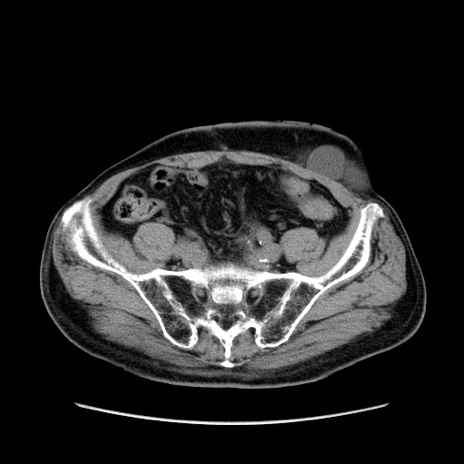

症例24(横断像)

【症例】80歳代男性

【主訴】左側腹部痛、嘔吐

【現病歴】本日早朝より左腹部に痛みあり。昼頃嘔吐認めたため、救急要請。

【既往歴】直腸癌(Mile手術)、胆摘

【身体所見】意識清明、BT 35.9℃、BP 221/93mmHg、SpO2 97%(RA) 、腹部:左ストーマ周囲に限局性の腹部膨隆あり。 膨隆部自発痛・圧痛あり・軟。

【データ】WBC 7700、CRP 0.09